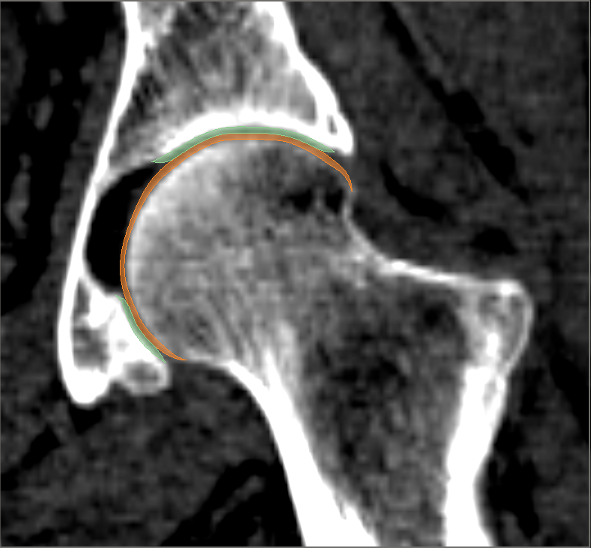

We have qualitatively verified that the articulating surfaces in all the ten HJs are detected correctly regardless of their anatomical variance using visual inspection of overlays as shown in Fig. 4. As desired, we observe a high degree of congruence between the opposing joint surfaces, meaning no gaps or overlaps in the cartilage-cartilage interface. Moreover, we observe a smooth transition towards the bone geometries as expected from the correct anatomy. The parameter values used to generate the cartilage from Fig. 5(a). The free parameters are the neighbourhood-size used to estimate the curvature of the bone (𝒩𝒩\mathcal{N}); the minimum and maximum curvature in the cartilage region (κmin,κmaxsubscript𝜅subscript𝜅\kappa_{\min},\kappa_{\max}; Eq. (2)); the distance parameter in mm𝑚𝑚mm (δ𝛿\delta; Eq. 1); and the number of times the outer boundary should be trimmed (Ntrimsubscript𝑁𝑡𝑟𝑖𝑚N_{trim}). Here, the curvature based parameters (𝒩,κmin,κmax)\mathcal{N},\kappa_{\min},\kappa_{\max}) are only used for the femur. See supplementary material for more visual comparisons.

Refer to caption

(a) Von Mises stress.

(b) CT scan overlay.

Figure 4: The von Mises stress patterns ((a)) and the generated cartilage imposed on the CT scan from which the bone was extracted ((b)). Notice the high level of congruence in the cartilage-bone interfaces and cartilage-cartilage interface.